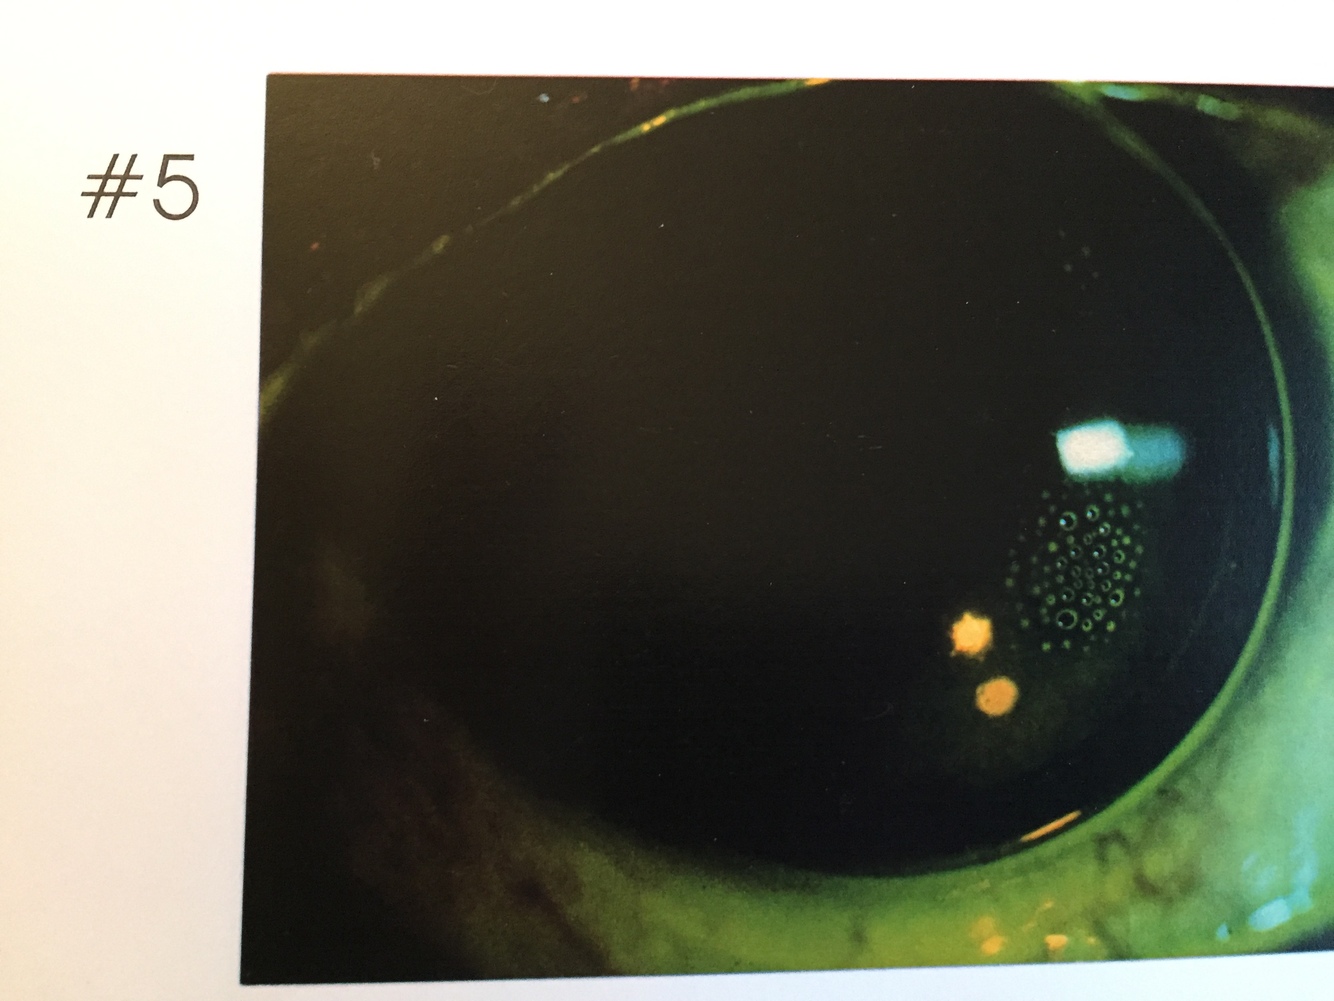

5.

Dimple vailing / lens too steep

Indentations of the epithelium resulting from air bubbles (under RGPs) or Mucin balls (under soft lenses). Most often seen with steep fitting RGPs.

Symptoms: None- mild irritation, may disturb vision if on visual axis.

Signs: Indentations display un-reversed illumination with white light. Multiple, focal areas of fx pooling

Refit closer to the corneal shape. Flatter BOZR, smaller diameter or change to toric back surface.